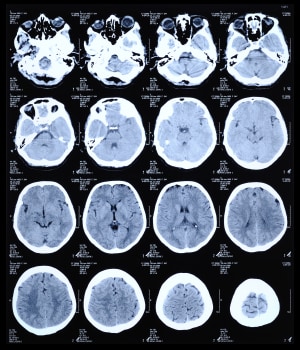

Magnetic resonance imaging (MRI) is a completely different way of viewing inside parts of the body. It relies on the way hydrogen nuclei respond to magnetic fields. Functional MRI (fMRI) is a specialized version used in the brain, tracking oxygen instead to image blood flow based on oxygenation levels.

This process works by placing the body in a strong static magnetic field so that all the nuclei are oriented in the same direction. A varying field is then created to perturb the atoms locally; this re-orients them from their starting position. When that varying field is removed, the cell processes back to the static position. Different cells relax at different rates, ranging from tens of milliseconds to over one second, and the decay signals given off as the cells move back – in the 1 to 300 MHz range – create the image (see Figure 5). It is these differences in the relaxation timing that allow the system to discriminate different kinds of tissues.

Figure 5: MRI image of the brain.